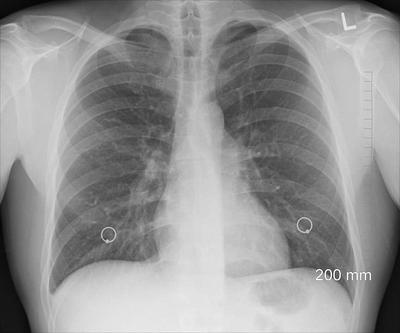

肋軟骨骨折 Ct

肋軟骨骨折 Ct のギャラリー

日々の症例 150 肋骨骨折

肋骨骨折的片子 医学影像学讨论版 爱爱医医学论坛

肋骨一根骨折的照片 第1页 一起扣扣网

肋骨骨折 你漏诊了吗 螺旋ct三维重建在胸廓骨折中的应用价值

断裂一根肋骨的ct图片 第1页 一起扣扣网

肋叉骨断了ct照片 第1页 要无忧健康图库

肋骨线性骨折ct图 第1页 一起扣扣网

肋骨挫伤的ct 第1页 一起扣扣网

肋骨骨折是個坑 就看挖的深不深 每日頭條

肋骨骨折 你漏诊了吗 螺旋ct三维重建在胸廓骨折中的应用价值

断裂一根肋骨的ct图片 第1页 一起扣扣网

肋骨骨折 影像ppt